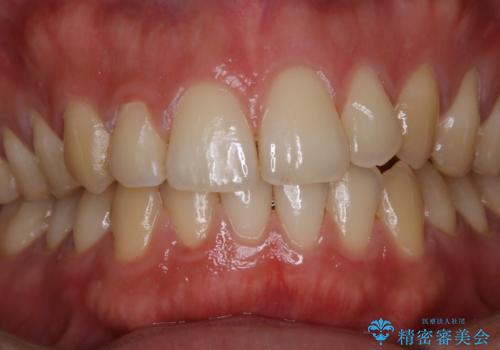

- マスクの着用により、以前より口臭が気になるとのことでした。しっかりと全体的なクリーニングを希望されたため、PMTC60分コースを行いました。

PMTCとはProfessinnal Mechanical Tooth Cleaning・専門器具による歯の機械的な清掃です。

バイオフィルム(細菌の塊)を破壊し、歯の表面をツルツルにすることでお口の中の細菌数を減らし歯周病のリスクが定着するのを防ぎます。更に、歯に新しい汚れがつきにくい状態になります。

バイオフィルムが除去されると、ご自身本来の歯の表面になります。PMTCをすることで口臭予防にもなり、定期的に行うことが大切です。